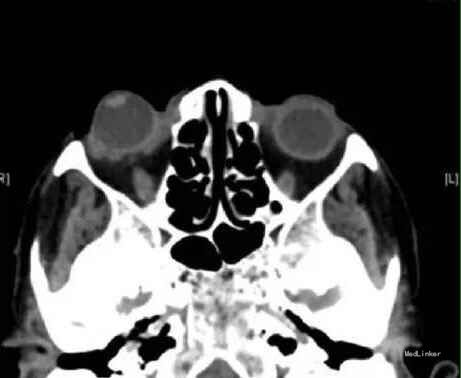

患者女,65岁,3小时前右眼被门把手打伤后剧烈疼痛。

右眼视力:HM,IOP:54mmHg,上下眼睑均位于脱位的眼球后,角膜水肿。

诊断:外伤性眼球脱位 处理:用代马尔眼睑拉钩使眼球复位